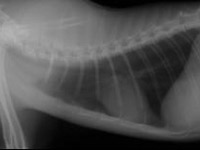

レントゲン検査は、膵炎以外の疾患を除外するのに有用ですが膵炎の診断に直結する所見は得られません。

レントゲン検査は、肝臓全体の大きさや形状を見る検査です。超音波検査は、肝臓実質部分をより詳細に検査することができます。血管・胆管の走行や胆嚢の内部構造まで確認できます。しかしながら、超音波で確定診断を

胸部レントゲン検査により縦隔の腫瘤や胸水の有無を確認します(縦隔型)。腹部レントゲンにより腹部臓器の大きさや位置を確認します(消化器型、多中心型、腎臓型)。超音波検査は、腹部臓器を